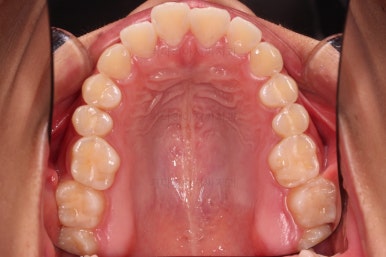

1. 초진 시 입안의 모습 평가

부산연산역치아교정 키다리아저씨치과에 처음 내원했을 당시의 입안의 모습이비다.

앞니 약간, 어금니쪽 약간 삐뚤어진 것, 그리고 위아래 앞니가 약간 뻗쳐 보이는 양상 이외에는 매우 가지런해 보여서 교정치료를 굳이 왜 하시려고 하지? 라고 생각될 정도의 치열 상태였습니다.